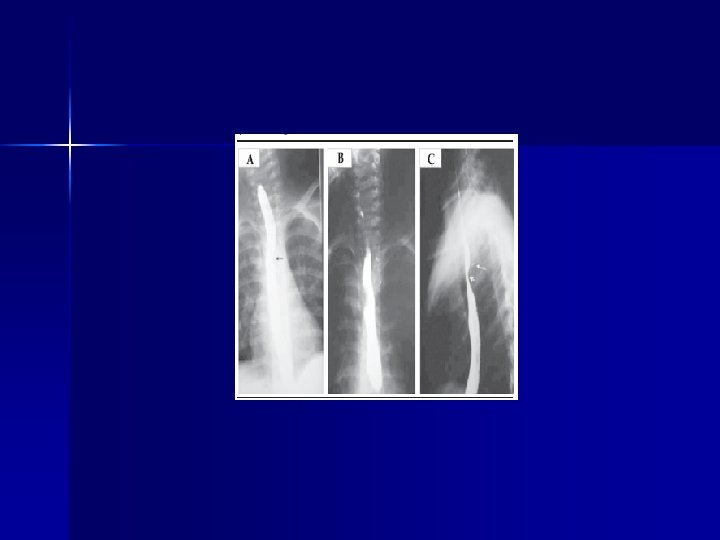

CUELLO n Si penetra Platisma: -Indicación de exploración en SOP -Angiografía -Faringo – laringoscopía -Esofagoscopía -Esófagograma: medio hidrosoluble luego Bario -TAC

CUELLO Rx cervicales: -AP y laterales -Odontoides -Rx dinámicas: flexión y extensión para descartar lesiones ligamentos n TAC (Scan cervical): -Si hay sospecha de lesión n